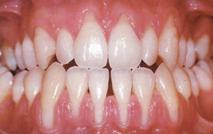

Генерализованная рецессия (рис. 9) может быть проявлением физиологического процесса старения, когда происходит так называемое «прорезывание зубов».Многие конституциональные особенности, такие как мелкое преддверие полости рта, тонкая кортикальная пластинка альвеолы с явлением фенестрации, механическая травма десневого края пищей, зубной щеткой, плохо прилегающими коронками и пломбами, а также появление супраконтактов зубов приводят к генерализованной потере десны.

Генерализованная рецессия чаще всего является результатом длительно протекающего пародонтита безвыраженных пародонтальных карманов, а также атипичных форм проявления быстропрогрессирующегопародонтита, при котором потеря десны может быть единственной жалобой пациента.Данный процессвстречается у пациентов при незначительной зоне прикрепленной десны, вестибулярном расположениианатомически крупных зубов и выраженном сокращении круговой мышцы губы (чаще всего это встречается у актеров, оперных певцов и у представителей других специальностей, где необходима профессиональная дикция и постоянная работа мимической мускулатуры).Наличие воспалительного процесса и пародонтальных карманов при наличии десневой рецессии способствует подвижности зуба,делая его более уязвимым к жевательным нагрузкам.Нередко травматическая ситуация (перегрузказуба, наличие супраконтактов) приводит к десневой рецессии в тех участках, где возникают боковые силы, при этом зуб достаточно долго сохраняет устойчивость.Гингивальная рецессия может быть интерпроксимальной, создающей пространства, в которых аккумулируются остатки пищи, зубной налет и бляшка, в результате может возникать вторичный воспалительный процесс.